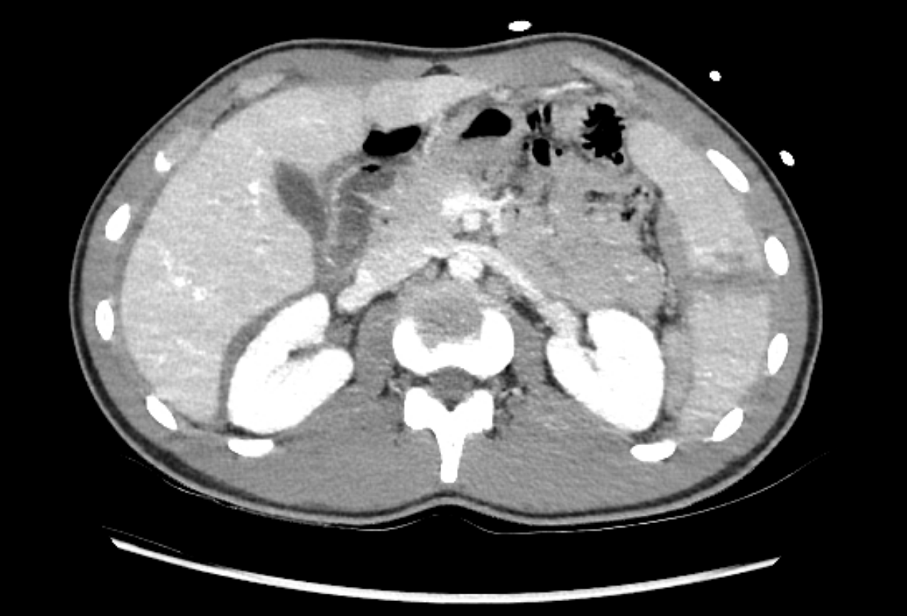

Le rapport du CT thoraco-abdominal fait état de lacérations post-traumatiques spléniques étendues classées grade IV selon AAST (cf tableau 2), atteignant le hile splénique, associées à un probable hématome sous capsulaire splénique médial et un saignement actif veineux au sein de lacération, un hémopéritoine abondant de localisation péri hépatique, péri splénique ainsi que dans le petit bassin et du liquide libre de densité hématique au sein de la gouttière pariéto-colique gauche.